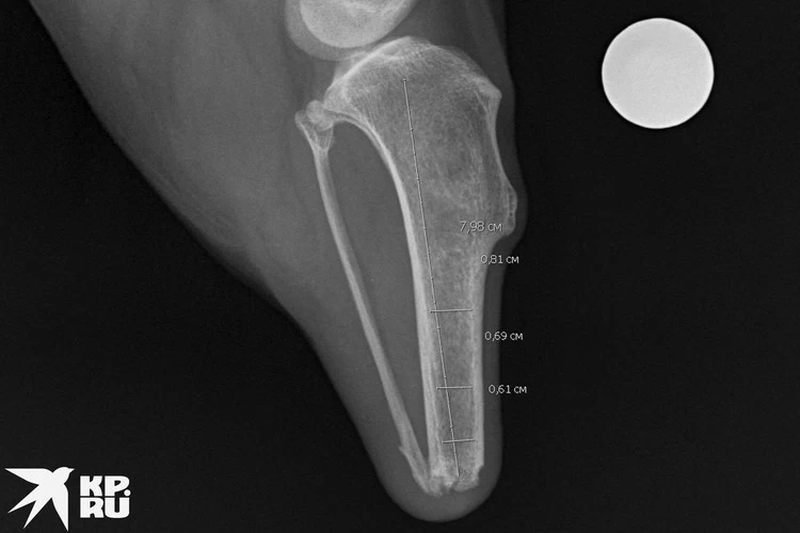

«Пришлось изготавливать протез только на основе рентгеновского снимка. Мы его обработали, загрузили в программу-планировщик и сделали 3D-модель. Потом уже отпечатали и отправили заказчику», — объяснил КП-Новосибирск Сергей Горшков, ветеринарный врач-хирург.

Казалось бы, уже все решено и скоро Хопи будет бегать на четырех лапах, но возникли проблемы. У Павла был только рентгеновский снимок, а еще нужна была томография. В маленьком городе сделать ее возможности не было.